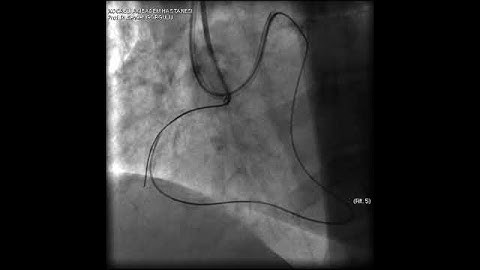

Aortic dissection and radial rupture during retrograde CTO PCI: Management of complications VİDEO 23